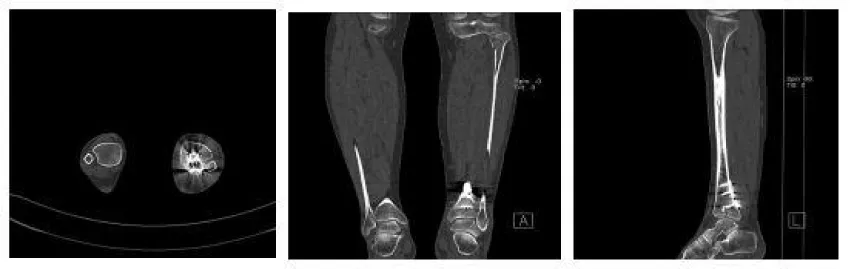

The anesthetic for the operation was lumbar anesthesia. A posterolateral approach was used to expose the Volkmann fracture. An anterior tibial approach was used to expose the Tillaux-Chaput fracture. The inferior tibiofibular joint was checked carefully. Fractures were reduced and then fixed. Volkmann fracture was fixed by buttress plate, and Tillaux-Chaput fracture was performed by hollow screw. Hook test intraoperative was negative. Anatomical reduction and perfect stability were confirmed by X and CT postoperatively (Figures 6.7). CT scan in the transverse section confirmed that the anterior and posterior edge of the distal fibula is in an arc with the fractures of the tibia. It meant there was no dislocation of the distal fibula. The anterior and posterior ligaments of the inferior tibiofibular ligament are in good condition.

Three weeks after surgery, the patient is required to touch down weight-bearing in a plaster splint. Patients are then allowed partial weight-bearing after six weeks and progress to weight-bearing. Ankle joint function exercises can be done three weeks after surgery. X noted that the fracture healed without shortening or rotation of the fibula when twelve weeks after surgery (Figure 8). The AOFAS score is 92 at twelve weeks follow-up [7,8].